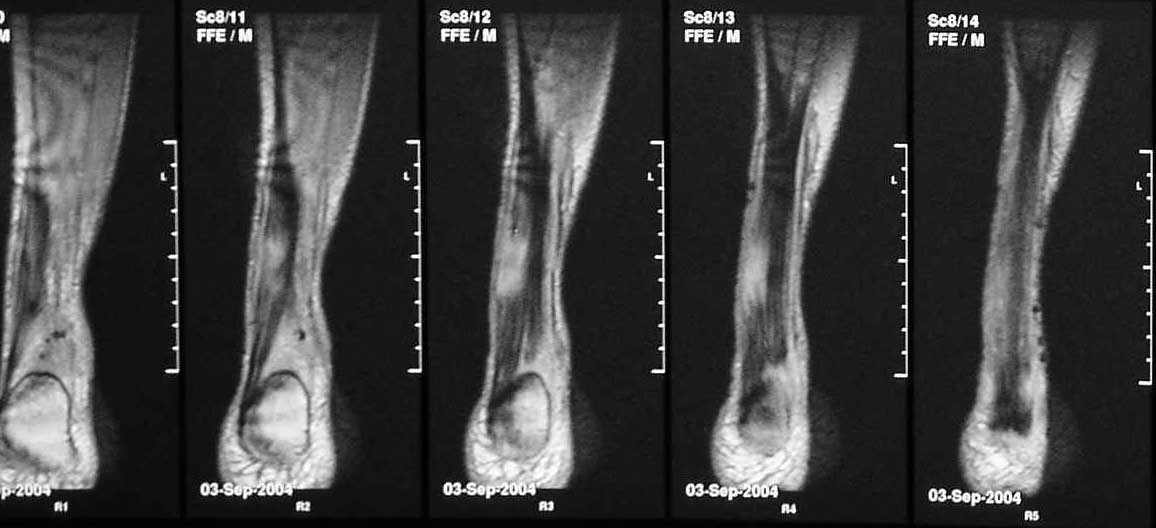

В сентябре сделана МРТ, цитирую заключение: "по внутренней поврехности сухожилия на уровне средней трети определяется очаг с неоднородной гиперинтенсивностью сигнала на T2W и изоинтенсивного сигнала T1W неправильной форму. Прротяженность очага до 43 мм в вертикальном диаметере. В центральной части очага на протяжении до 22 мм определяется прерыв и диастаз волокон ахиллова сухожилия. Заключение: Частичный дегенеративный разрыв ахиллова сухожилия, тендинит".

Подобное решение основано на результате магнитно ядерного резонанса который показывает что разрыв сухожилия не превышает 50 процентов от общего диаметра